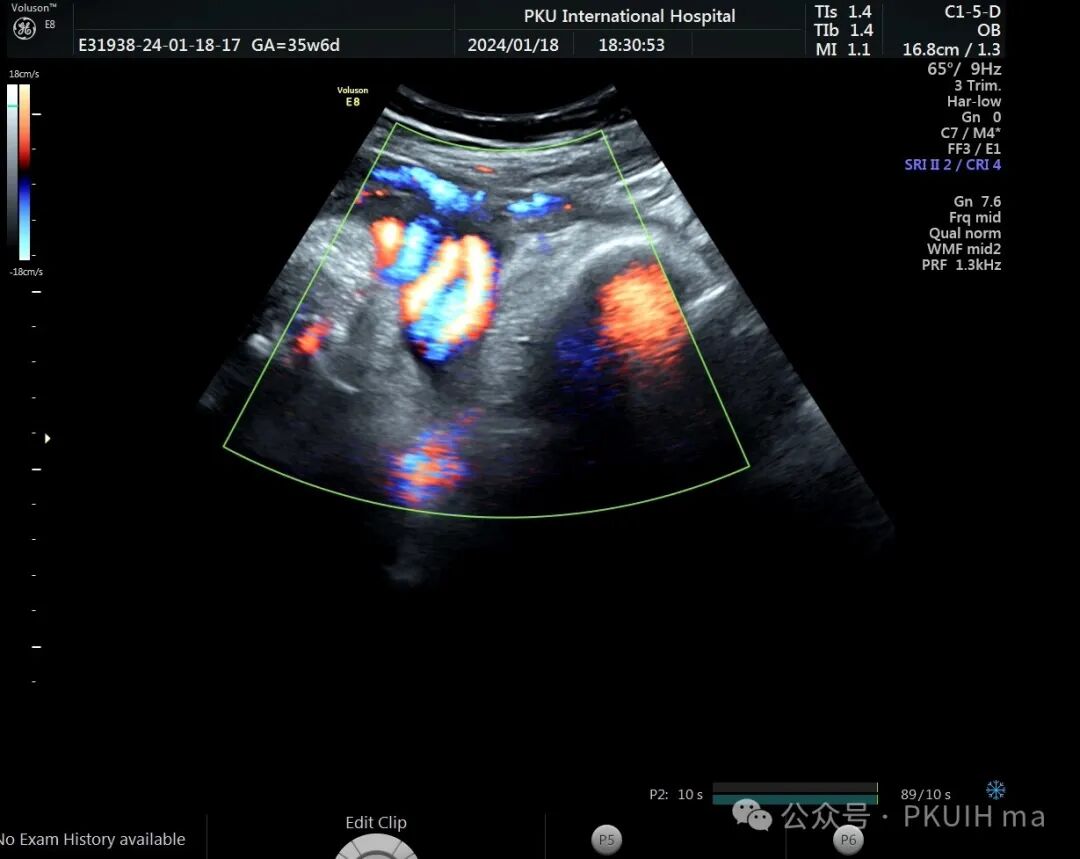

前两天碰到一孕妇胎动减少来诊,孕妇自述下午两点开始发现胎儿无明显胎动,吃了甜的食物和改变姿势还是不怎么动,随于下午六点左右来诊。超声发现胎儿绕颈两周以上且绕的较紧,检查中发现胎儿心率快,胎儿无明显胎动,绕颈处脐动脉血流加速时间延长,胎儿大脑中动脉阻力低,反复测量两侧大脑中动脉阻力均低。胎心监护也不好,随后产科采取紧急剖宫产。

脐带绕颈两周以上,绕的特别紧,感觉脖子都被勒细了,脐带与皮肤之间无任何空隙。绕颈处血流加速时间延长,说明可能存在交锁并出现了脐动脉局部狭窄